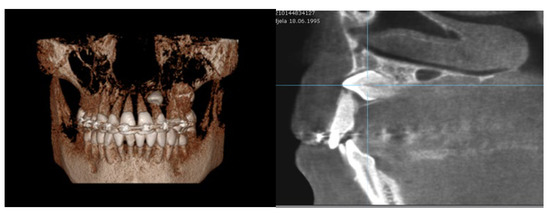

Therefore, the measured distance from the canine cusp tip to the occlusal line (11.7 ± 3.6 mm) is considered to be a significant parameter, since it shows statistical significance with respect to RR in adjacent teeth; namely, the higher position of the impacted canine causes a more severe degree of RR (Figure 5). The mean values for the distance from canine cusp tip to midline (9.25 ± 4.4 mm) are also a statistically significant parameter concerning the severity of RR.

Figure 5.

Horizontal position of left permanent maxillary canine associated with severe RR on lateral incisor (3D volumetric scan and sagittal plane).

There was no statistical significance between the vertical position of the crown and the severity of RR, but there was a statistically significant correlation between the severity of RR and the degree of the horizontal overlap of the canine cusp and adjacent teeth, the greater degree of overlap leading to advanced severe resorption. The results for RR in the first premolars are also different. There was statistical significance for the horizontal position of the impacted canine, angulation to midline and distance to occlusal line (Table 4).